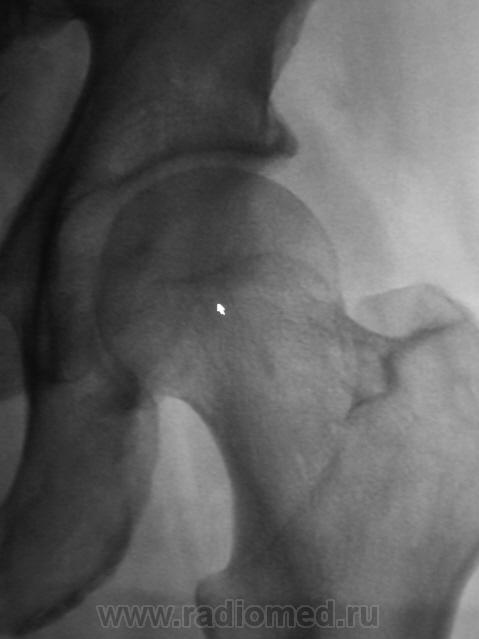

Пациенту снимки в трех проекциях делались не за "просто так". Выставлю все рядышком.

Укладка практически идеальная, а головка, если внимательно присмотреться, не на месте. А невидимость линии уплотнения - это тоже один из сюрпризов шейки бедра. Хотя, искать ее надо на первых снимках, да и то не всегда увидишь. Через месяц искать нужно тонкую полоску разряжения.

Нет не "рассужу". Придерживаюсь библейского - "Не судите, да не судимы будете". Снимки все выложу.

А полоска разрежения видна.